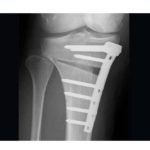

Debate: High Tibial Osteotomy for Unicompartmental Arthritis

High Tibial Osteotomy- Planning and Indications